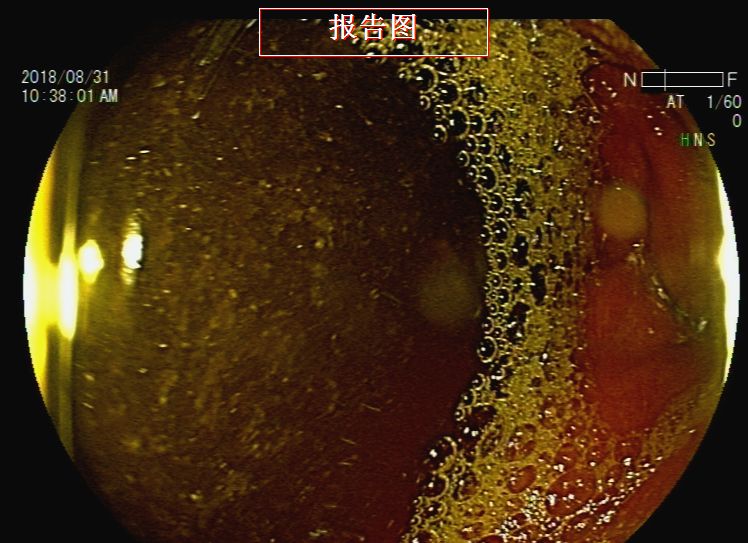

胃镜检查:反流性食管炎,胃内液体潴留,吻合口前区黏膜下隆起——考虑转移灶压迫,近端小肠梗阻(图9、图10、图11、图12、图13)。根据消化道造影及内镜检查结果,考虑梗阻部位在近端小肠,吻合口前区虽有较大的隆起灶,但是内镜通过可,暂不处理。

图12 胃镜检查见近端小肠梗阻

图13 胃镜检查见近端小肠梗阻